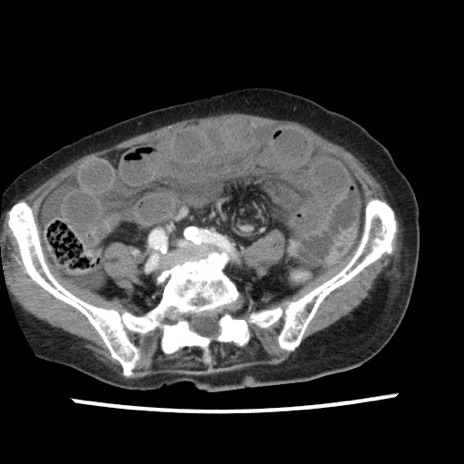

症例1(横断像)

【症例】80歳代女性

【主訴】腹痛

【現病歴】8時間前から腹痛あり来院。

【既往歴】糖尿病、脂質異常症、子宮体癌にて子宮全摘術

【身体所見】意識清明・会話良好だが腹痛で苦悶様、全腹部にわたって反跳痛と圧痛あり

【データ】WBC 13600、CRP 0.14、LDH 224、CK 90